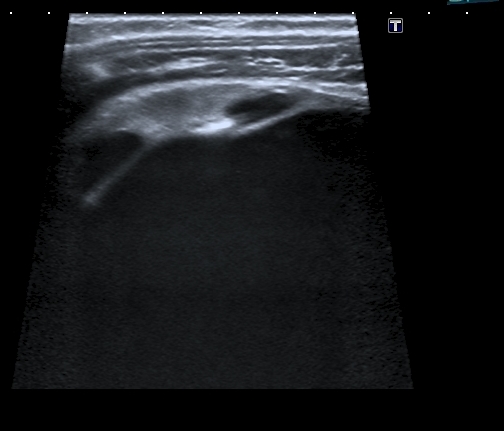

Сканирование высокочастотным датчиком  - резидуальная паренхима